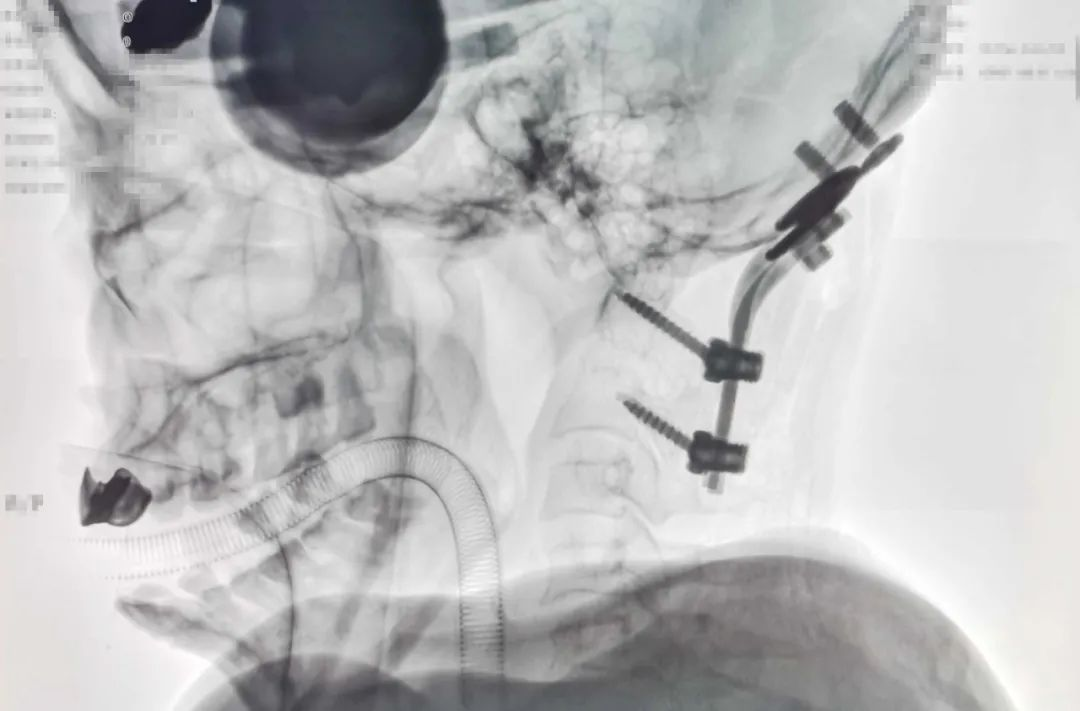

颅底凹陷症通常导致颅后窝和上颈部椎管有效空间缩小,颈延髓受压,故治疗目的在于给予复位融合固定,恢复脊柱稳定,减轻延髓受压。完善术前准备,未发现患者有明显手术禁忌,与患者家属积极沟通后,大骨科主任陈子华带领脊柱外科团队为患者实施了颈后路寰枢关节复位椎弓根钉棒固定+枕颈融合+C2椎板切除减压内固定术。

▲术后C型臂透视下寰枢椎关系